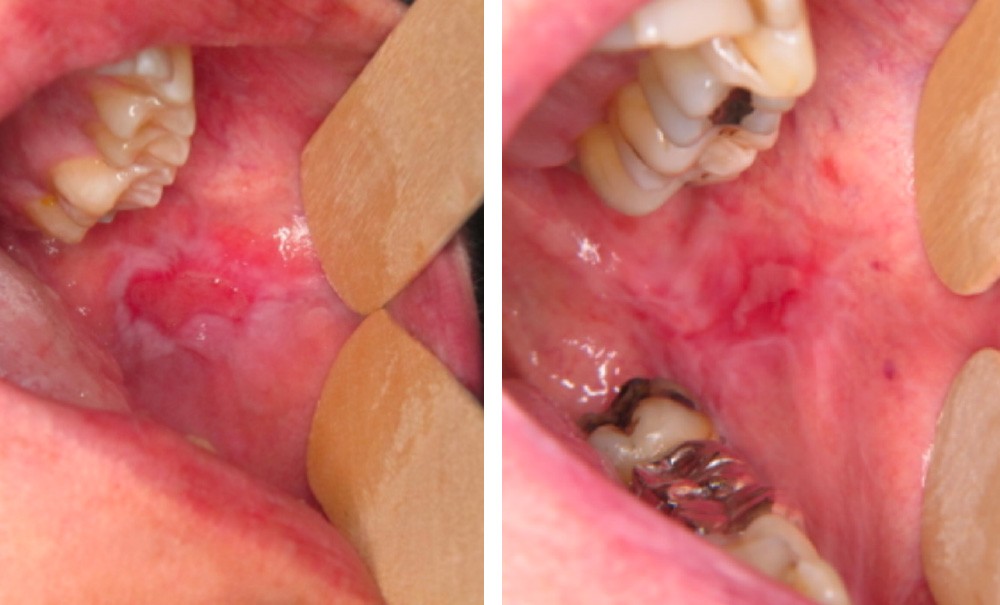

Examen clinique. Il révélait une ulcération, de 1,5 cm de grand axe, de la joue bordée par une muqueuse atrophique et kératinisée.

Synthèse. La lésion est caractéristique d’une réaction lichénoïde survenue dans le cadre d’une maladie du greffon contre l’hôte (Graft-Versus-Host Disease, GVHD).

La GVHD est l’une des principales complications de l’allogreffe de cellules souches hématopoïétiques. Elle est secondaire à une réaction des cellules immuno-compétentes du donneur contre les cellules du receveur. Les lésions buccales de la GVHD ont une grande ressemblance clinique et histologique avec le lichen plan idiopathique. Le contexte de survenue permet de faire le diagnostic.